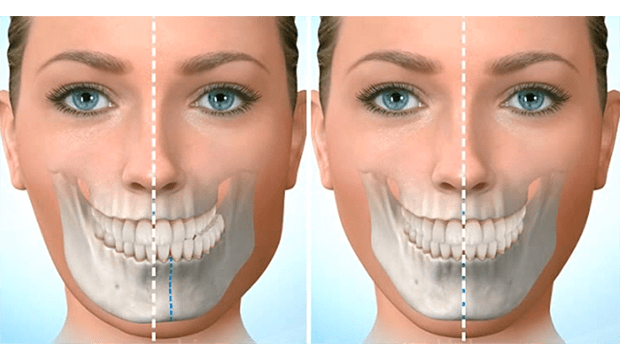

- Küçük çeneler ( micrognati ), underbite’ler (az ısırma) ,overbite’ler (örtülü kapanış) ve çapraz kapanışlar gibi yüz asimetrileri varlığında

Ortodontist ve çene cerrahı, tedavi planını geliştirmek için birlikte çalışır. Dişlerin ve çenelerin röntgenleri, resimleri ve modelleri, bu ameliyatın planlamasının bir parçasıdır. Bazen oklüzyonün (alt- üst dişler arasındaki kapanış) tam sağlanamadığı durumlarda ,ilgili dişlerde selektif mölleme ( aşındırma ) yada kaplama tedavisi uygulana bilinir.

Çene ameliyatı üst çene, alt çene, çene ucu ( genioplasty) veya bunların herhangi bir kombinasyonu ile yapılır.

- Alt ve orta yüzün daha dengeli görünümü